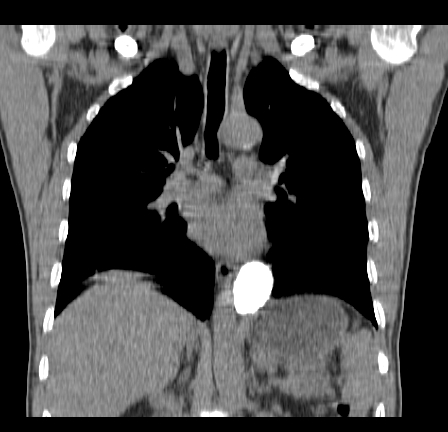

以下是引用影像孺子牛在2009-5-20 23:18:00的发言:[br]左侧后心膈角处类椭圆形钙化灶,最常见的是淋巴结钙化,但太大了不支持,其它如食管囊肿钙化、实性畸胆瘤等。何东西钙化真不好定。

以下是引用zbp537在2009-5-20 20:52:00的发言:[br]钙化灶,来源不好说。